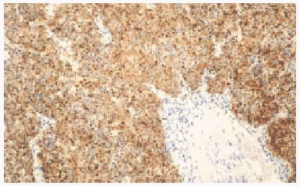

Tras la realización de técnicas de inmunohistoquímica, se observó positividad frente a queratinas de bajo peso molecular (citoqueratina 20) en el 66 % de los casos (fig. 4), con disposición característica de punteado perinuclear, así como una amplia positividad a los marcadores neuroendocrinos con el 100 % a la cromogranina (fig. 5) y el 82 % a la enolasa neuronal específica (fig. 6).

Fig. 4.--Tinción positiva para citoqueratina 20.

Fig. 5.--Tinción positiva para cromogranina A.